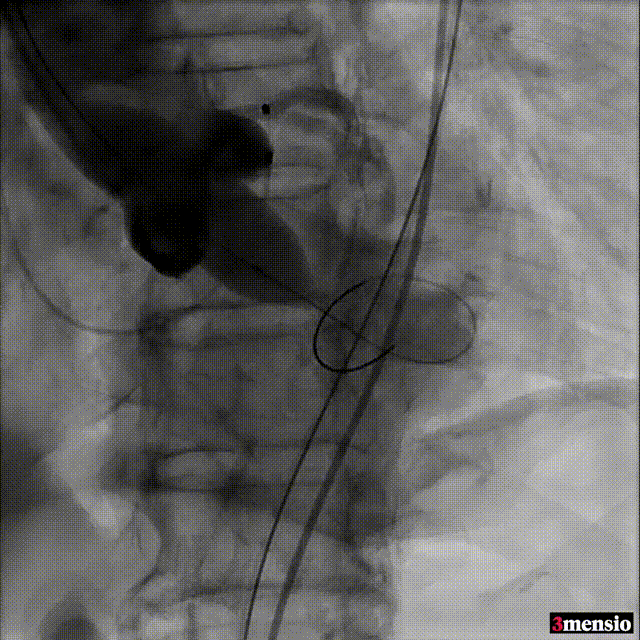

跨瓣

20mm球囊预扩

唐熠达教授团队对病例进行多学科综合分析评估决定行一站式PCI+TAVI手术,结合患者91岁高龄,主动脉根部结构及双侧劲动脉粥样硬化斑块形成,脑动脉硬化情况采用20mm球囊预扩,拟植入VenusA-Valve L26瓣膜。